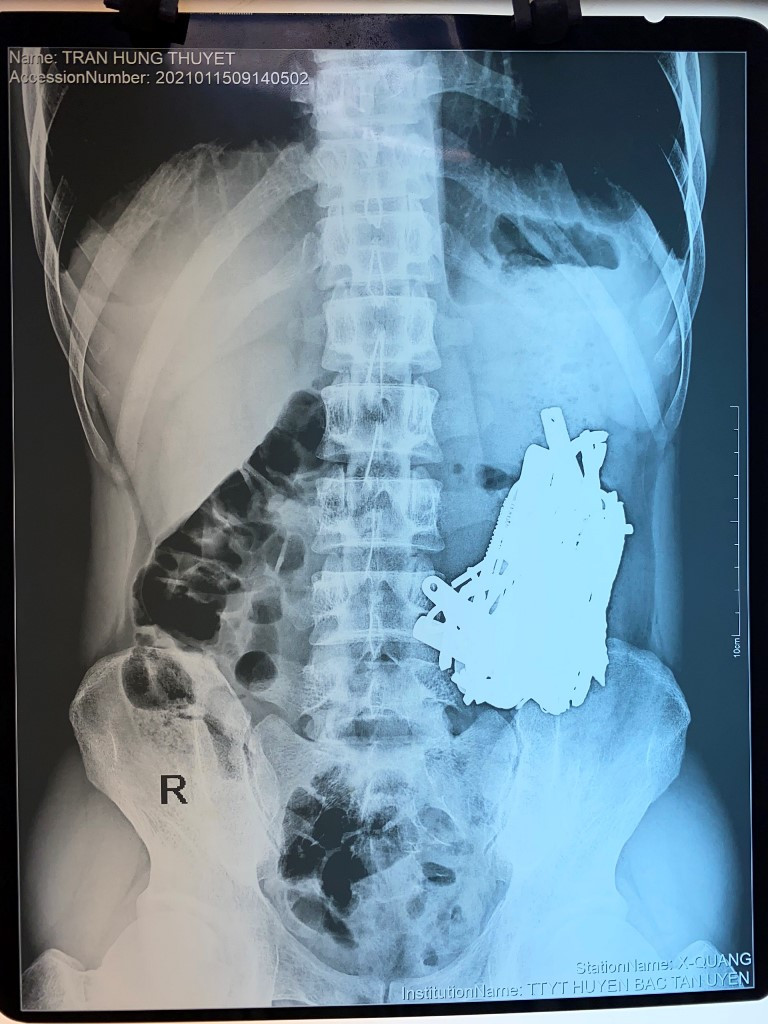

Bác sĩ 'choáng' khi phát hiện vô số đinh, thìa, lưỡi dao trong bụng nam bệnh nhân ảnh 1Hình chụp XQuang phát hiện khối dị vật trong bụng (ảnh: BVCC)

Tình trạng đau bụng tăng dần lên vào Bệnh viện tuyến trước được chụp Xquang bụng và chuyển lên Bệnh viện Quân y 175 điều trị. Bệnh nhân được chẩn đoán là tổn  dạ dày do dị vật/ hội chứng Pica, được các bác sĩ khoa Ngoại bụng hội chẩn và tiến hành phẫu thuật lấy bỏ cho bệnh nhân.

Khi vào ổ bụng thấy dạ dày sa thấp, viêm dày bên trong có khoảng 1kg dị vật kim loại dã bị ăn mòn một phần như đinh, thìa, bấm móng nay, lưỡi dao, thỏi sắt, móc đồ..., bệnh nhân đã được lấy tất cả các dị vật ra ngoài, diễn biến sau phẫu thuật ổn định.